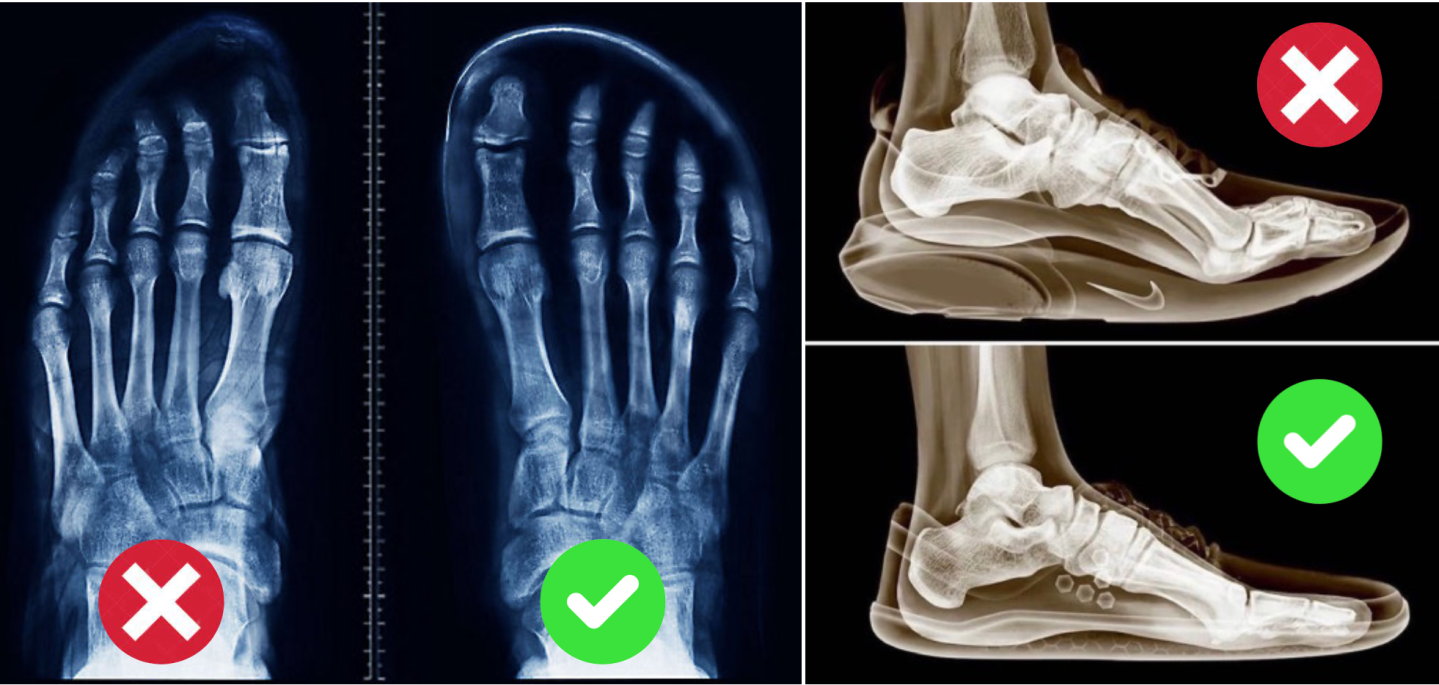

Wear shoes that are zero-drop with foot-shaped toe boxes to allow all the toes to be naturally splayed. Avoid shoes with heels that have uneven stack heights, and avoid shoes that have narrow/tight toe boxes.

Our feet are like the root system of a tree. Proper development of the feet can critically affect the posture, balance, nervous system development, physical/athletic performance, agility, and ultimately physical health of the body.

If the roots are not developed properly, the tree will lean, become unbalanced and not develop to its best form. This is especially important for children as their feet are still in the process of developing, we urge parents to have foot-shaped shoes with low stack height for their children from young, and allow them to go barefoot as much as they can. There are a lot of nerves on the bottom of our feet, minimally stacked shoes will allow those nerves to sense the ground so that the body can develop properly.

The goal is to develop feet that have natural splayed toes like the picture above.

For walking and low impact activities, it is best to use low stack height shoes for ground contact and feel. Higher stack height zero-drop shoes may be used for running and harder surface activities.